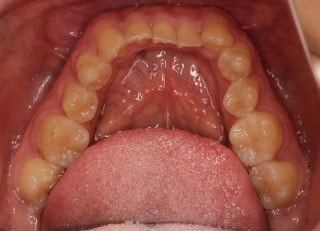

治療前